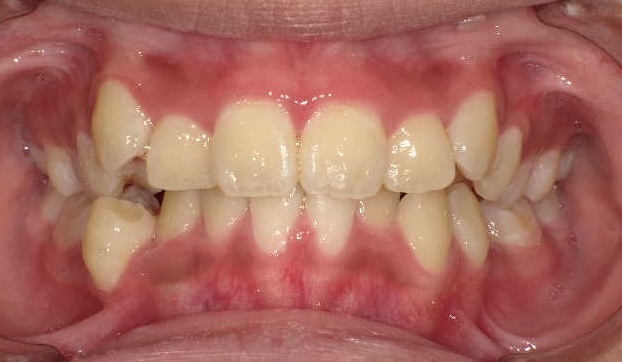

症例1-③

そこで当院では、ここからは、当院の成人非抜歯の技術を用いて、永久歯を抜くことなく(親知らずは除く)治療をゴールまでもって行きます。

症例1-③の写真が完成時の所見です。いかがでしょう、口もとも美しくきれいな永久歯列の完成です。